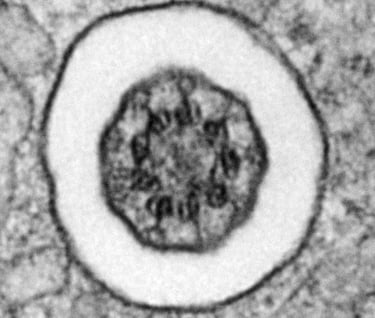

There is a cilium cross-section in there - do you see it?

Cilia and centrioles

Most every islet cell has a primary cilium and pair of centrioles. When we find them on an EM grid, it's a good day.

Axoneme cross-section

mouse islet